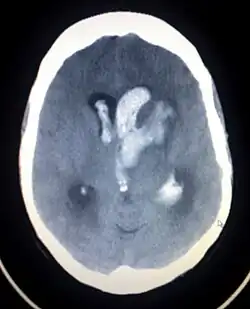

Intrazerebrale Blutung

Eine intrazerebrale Blutung (ICB, von lateinisch intra- ‚in‘ und cerebrum ‚Gehirn‘) ist eine Hirnblutung im Hirngewebe selbst. Intrazerebrale Blutungen treten meist plötzlich auf. Eine Hirnblutung ist eine hämorrhagische Schädigung, die die gleichen Symptome wie ein Schlaganfall (ischämische Schädigung) hervorruft. Jedoch sind dies trotz der gleichen Symptomatik zwei unterschiedliche Diagnosen.

Häufigste Ursache sind die als Folge des Bluthochdrucks auftretenden Veränderungen kleiner Blutgefäße (Arteriolosklerose). Weitere Ursachen können Veränderungen der Gefäße wie eine zerebrale Amyloidangiopathie oder Gefäßmalformationen sein, aber auch traumatische Schädigungen – insbesondere in Zusammenhang mit der Einnahme gerinnungshemmender Medikamente – spielen eine wichtige Rolle. Selten können entzündliche Erkrankungen des Gehirns oder Tumoren sich als ICB manifestieren. Auch wenn es sich bei Blutungen aus geplatzten Gefäßwandaussackungen, den zerebralen Aneurysmata, üblicherweise um Subarachnoidalblutungen handelt, können auch intrazerebrale Blutungen durch Aneurysmarupturen verursacht sein. Neben der Lokalisation ist die Größe der Blutung für die Prognose und eventuelle Therapiemaßnahmen wichtig. So werden bei supratentoriellen Blutungen 50 cm³ und bei infratentoriellen Blutungen 20 cm³ als kritische Grenze für den weiteren klinischen Verlauf angesehen. Ein weiteres prognostisch ungünstiges Zeichen ist der Einbruch der Blutung in das Ventrikelsystem, woraus Zirkulationsstörungen des Liquor cerebrospinalis resultieren können und der eine externe Ventrikeldrainage notwendig machen kann.[1]